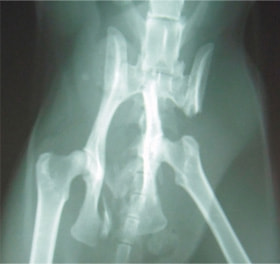

骨盤骨折 : 症例1 | 症例2 | 症例3 | 症例4